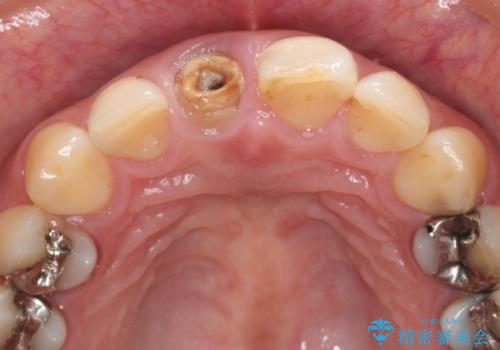

残っている歯質(歯の量)は非常に少ないものの、歯を抜かずに残したい希望が強く、また破折リスクが高いことも

ご理解いただいた上で歯を残しセラミック治療を計画します。

破折リスクを少なくするため前歯でかじったり硬いものを噛み切る等の行為は避けた方が良いとお伝えし、現状5年問題なく経過しています。